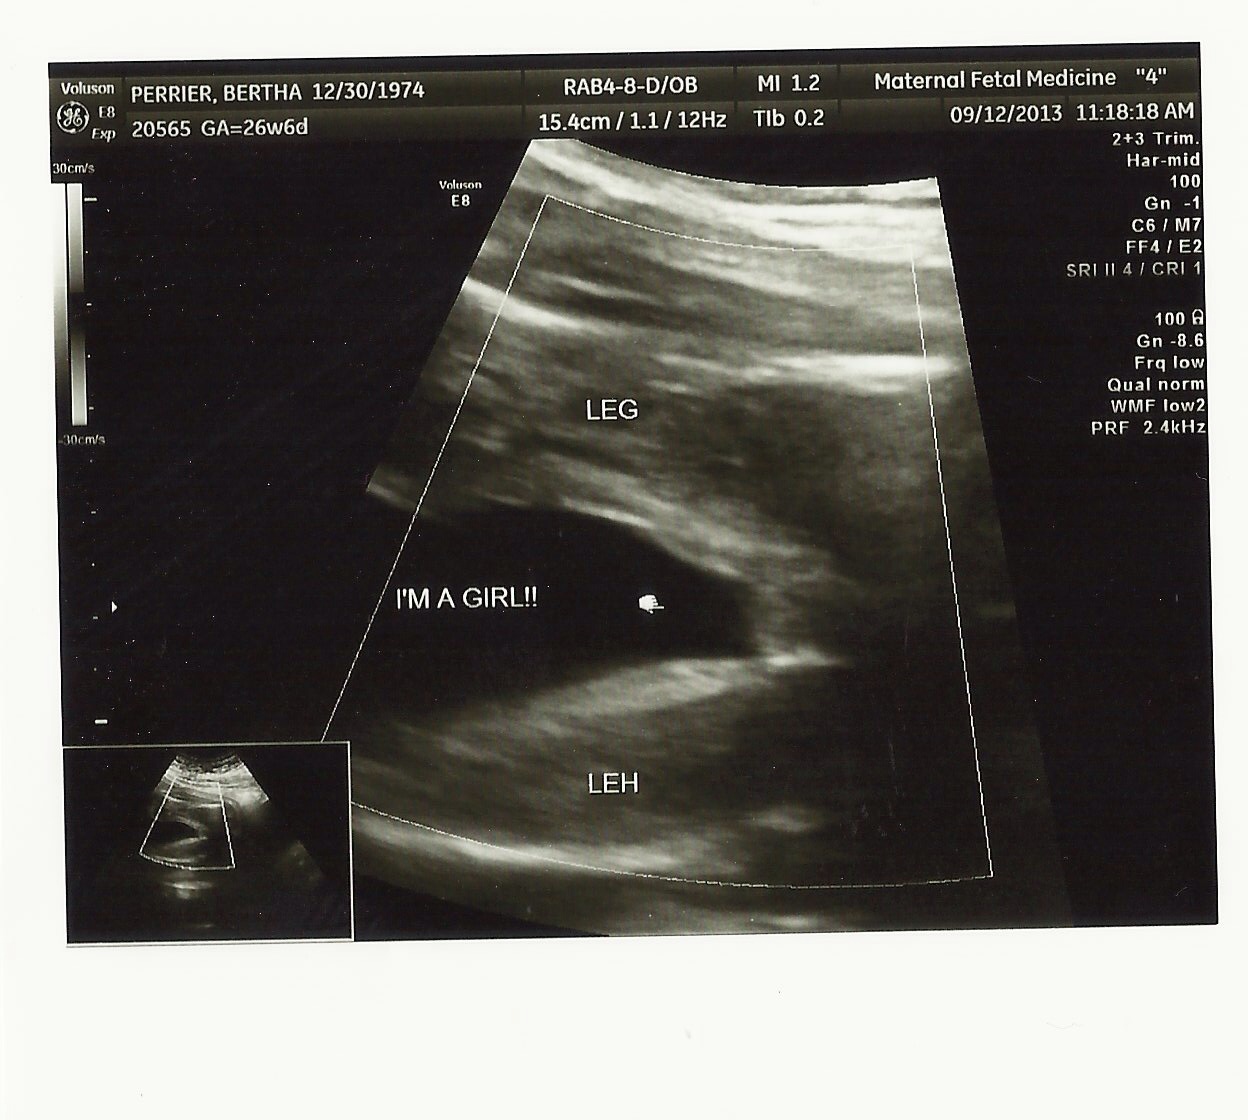

I had the same three lines for my girls.

That definitely looks like a girl to me.

oh defo girl